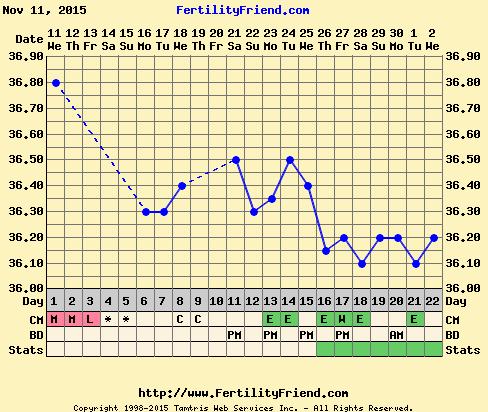

@fergiea ahooj jeej to je nadhera, tie nozicky a rucicky 🙂 🙂 este budes mat do Vianoc poradnu ci az po? 🙂 Dali ti aj tehotensku knizku? 🙂 Ja stale cakam na ovu, som si myslela ze po minulom cykle mi opät pride okolo 15dc ale zatial nic, teploty nizke a nejak sa nechcu rozhybat smerom nahor.. normalne sa bojim ze sa z toho vykluje anovulak ☹ ale hlien mam uz mozno tyzden co inokedy som mala uplne sucho tak som zvedava no

@fergiea jejoooo, krasna fotecka. Uz nech sa aj nam zadari. Mala by som mat teraz ovulku, meriam si BT, ale v tom grafe sa moc nevyznam a ani neviem ci to znaci ovulku. Ale ovu test som mala pred dvoma dnami pozitivny. Tak drz palceky a pekne nas ostatne nakaz 🙂 inak ako sa citis? už viac papas? lebo brusko ti krasne rastie 😉

@janikm ahoj moja 🙂 v utorok idem na odbery a uz mi daju tehu knizku. A hadam aj povedia co dalej ake vysetrenia. Hlavne ze nam bije srdiecko a rastieme aj napriek tonu, ze mi je hrozne zle. No trn graf mas riadne hnusny ☹ uz aby ovu prisla budem drzat palce aby to nebol anovulak.... moja 💜